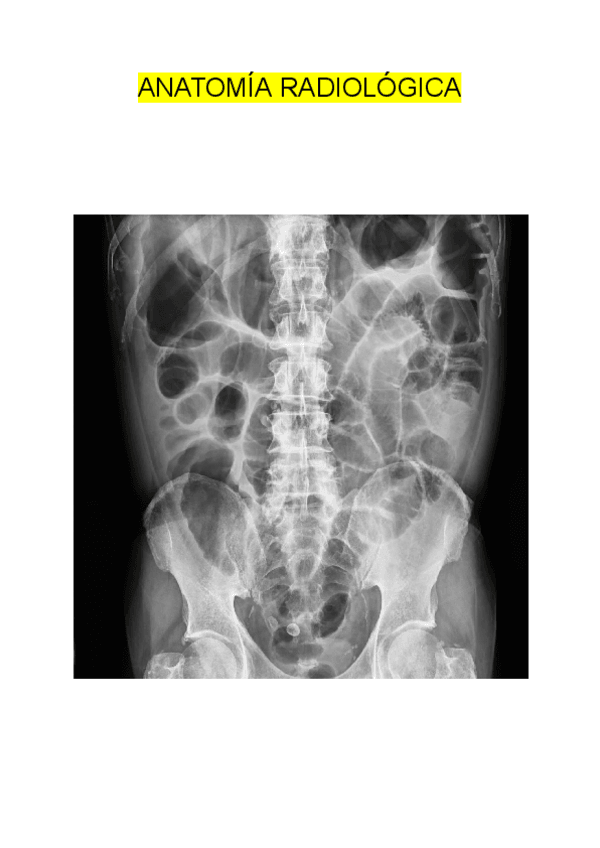

He publicado nuevos apuntes de Anatomía por la imagen: Imagenes-TC-RM-abdominal.pdf

63 páginas